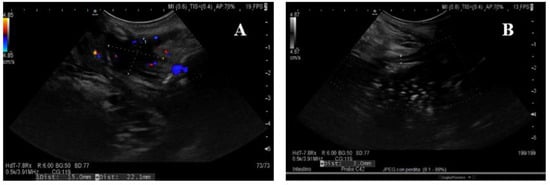

3.1. Ultrasound Features of CD